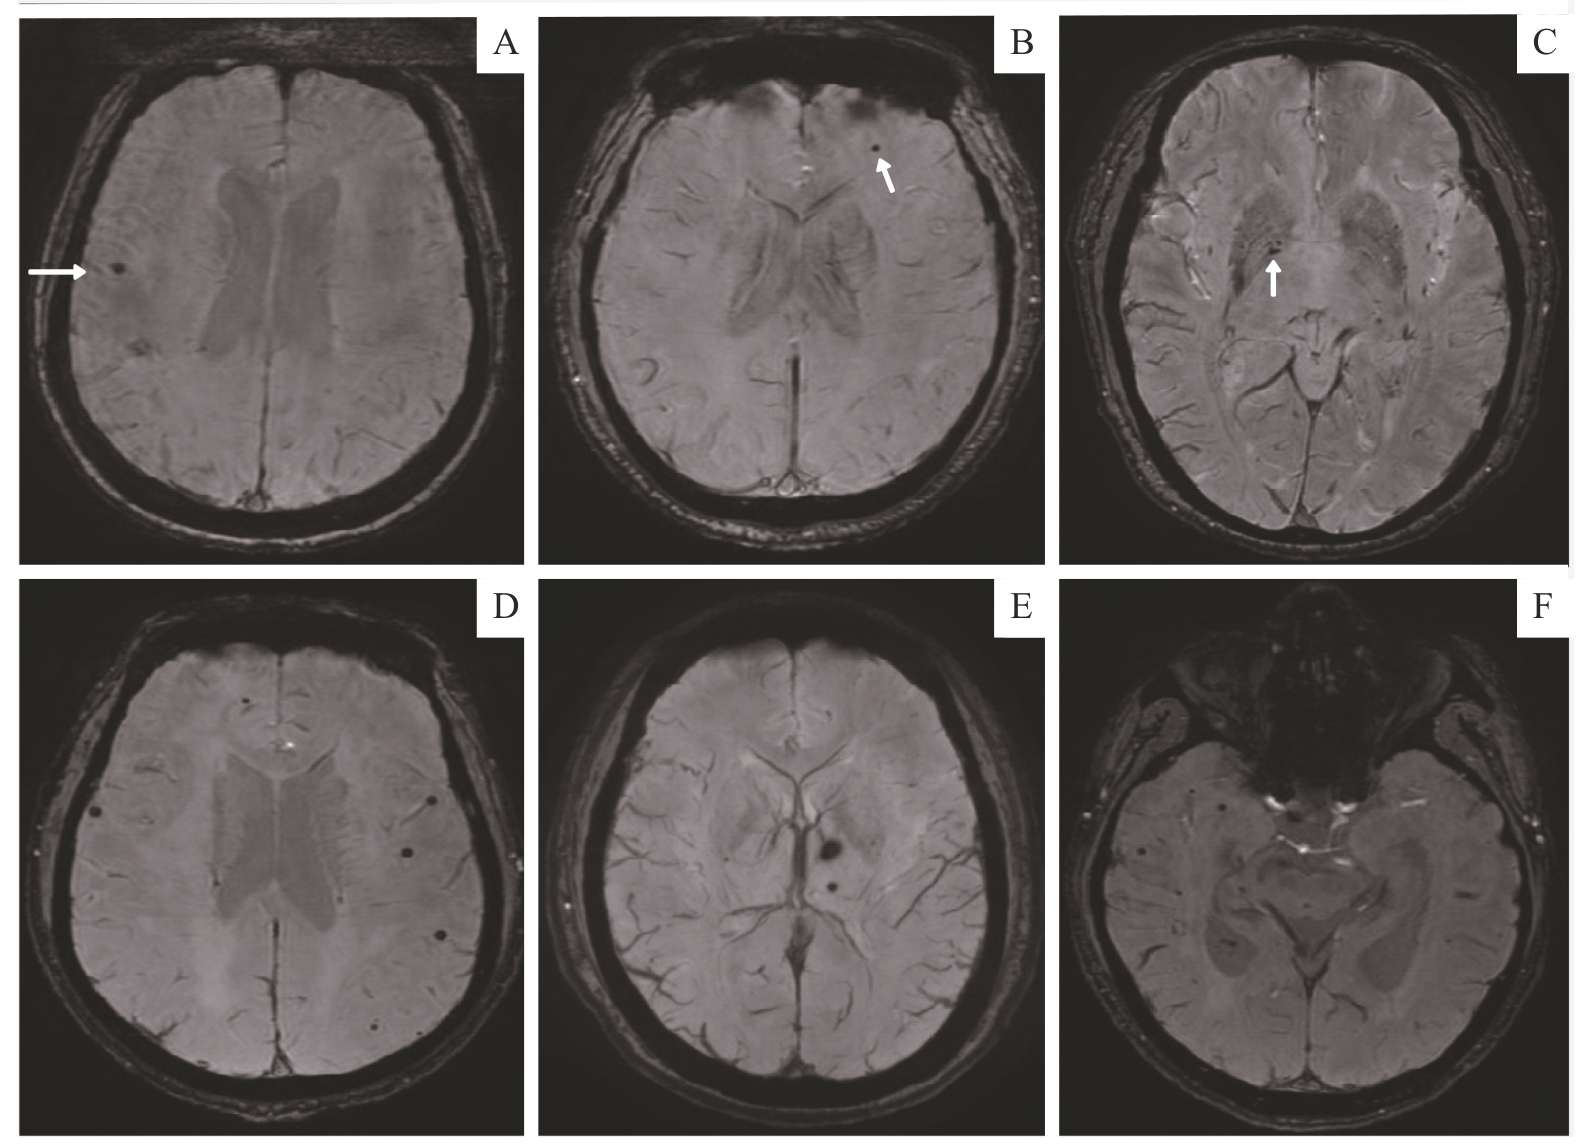

| 图2 2例患者不同脑区微出血灶的SWI图像 Note: A‒C. A 36-year-old female with ESRD who had undergone hemodialysis for 3 years had a few lesions in the right frontal lobe proximal cortex (A), the left frontal subcortex (B) and the right globus pallidus (C). The white arrows show the lesions in each brain region. This patient had no cognitive impairment, with a MoCA score of 28. D‒F. A 41-year-old male with ESRD who had undergone hemodialysis for 1.5 years showed multiple scattered CMBs in the frontal, temporal and occipital lobe (D and F), as well as in the left basal ganglia (E). This patient had cognitive impairment, with a MoCA score of 17. |

| Fig 2 SWI images of CMBs in different brain regions in two patients |